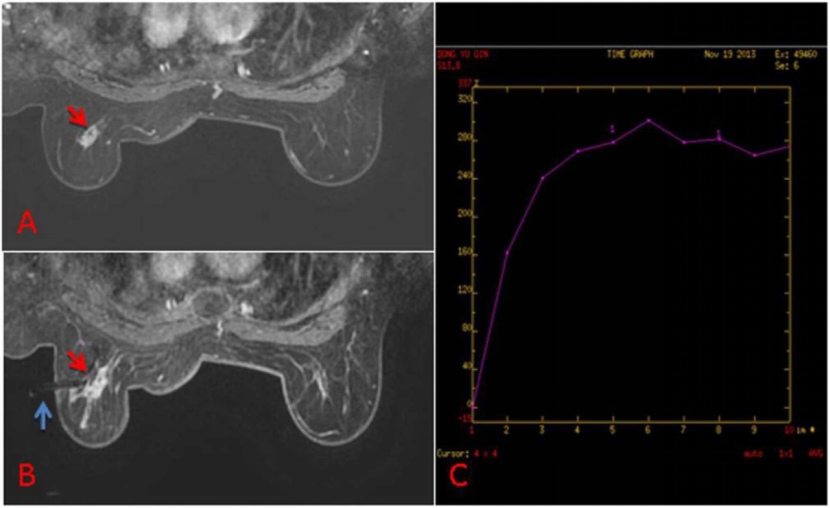

下面列举几个病例的MRI图像:

病例1:63岁女性,T1加权脂肪抑制增强MRI显示左乳不规则肿物,可疑恶性,BI-RADS 5级,在超声及乳房X光检查中均未发现 (A);病灶(红色箭头)经MRI引导下VABB(蓝色箭头)确诊为浸润性导管癌 (B);动态增强MRI时间-信号强度曲线(TIC)表现为“快升平台型” (C)。